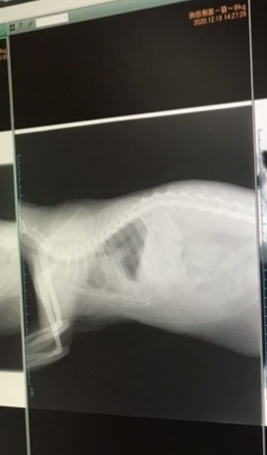

胸のあたり白くくもっているところがお水がたまっている箇所です。

健康な猫ちゃんは黒く空洞がしっかり映ります。

空洞ももっと範囲が広いです…

お水を抜いて3日後にレントゲン検査してもらいました!!

最初の画像より少し胸が綺麗になっていて投薬が効いている感じです!

ただ左側がまだ白くくもっています。